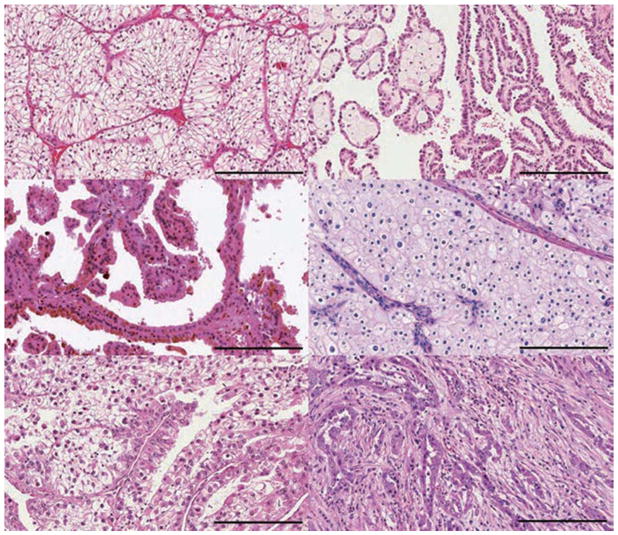

腎細胞癌 (RCC) 是一組源自腎小管上皮細胞的異質(zhì)性腫瘤,是全球 10 種賊常見的癌癥之一。在過去二十年中,RCC 的基因解碼組織病理學(xué)和分子表征方面的重要進展變革了腎細胞癌診斷及其分類。發(fā)病率≥5% 的主要亞型是透明細胞腎細胞癌(RCC)(ccRCC) 、乳頭狀腎細胞癌(RCC)(pRCC) 和嫌色細胞腎細胞癌(RCC)(chRCC)  (如圖1). 其余亞型非常罕見(每種亞型的總發(fā)病率≤1%),如果腫瘤不符合任何亞型診斷標準,則將其指定為未分類 RCC(uRCC,總發(fā)病率約為 4%)。ccRCC 是賊常見的亞型,占腎癌死亡的大部分,是佳學(xué)基因腫瘤基因檢測及基因解碼的重點。實際上,由于透明細胞組織學(xué)在轉(zhuǎn)移性疾病中占主導(dǎo)地位 (83–88% ) ,出于臨床試驗的可行性,具有非透明細胞組織學(xué)的腫瘤已被歸類為“nccRCC”, 表1) 。此外,基因解碼在腎細胞癌基因組研究揭示了 ccRCC 腫瘤內(nèi)和腫瘤間異質(zhì)性的明顯復(fù)雜性,這可能導(dǎo)致臨床試驗所產(chǎn)生的結(jié)果的差異性。

圖1:RCC 的不同亞型

大約 75% 的腎細胞癌 (RCC) 是: a、| 透明細胞腎細胞癌(RCC)(ccRCC)。b、 | 乳頭狀腎細胞癌(RCC)約占所有腎癌的 15%,根據(jù)染色特征分為兩種類型:b | 1 型(嗜堿性)和 c | 2 型(嗜酸性)。d | 嫌色細胞腎細胞癌(RCC)約占腎腫瘤的 5%。其他次要亞型包括 e | MiT 家族易位腎細胞癌(RCC)和 f | 集合管 RCC。其他次要亞型包括髓質(zhì) RCC、透明細胞乳頭狀 RCC、獲得性囊性病變相關(guān) RCC、腎小管囊性 RCC、粘液性管狀和紡錘體 RCC、琥珀酸脫氫酶缺陷型 RCC、遺傳性平滑肌瘤病、腎細胞癌相關(guān)腎細胞癌(RCC)和嗜酸細胞瘤。不屬于這些類別的腫瘤被指定為未分類 RCC。比例尺 = 200 微米。